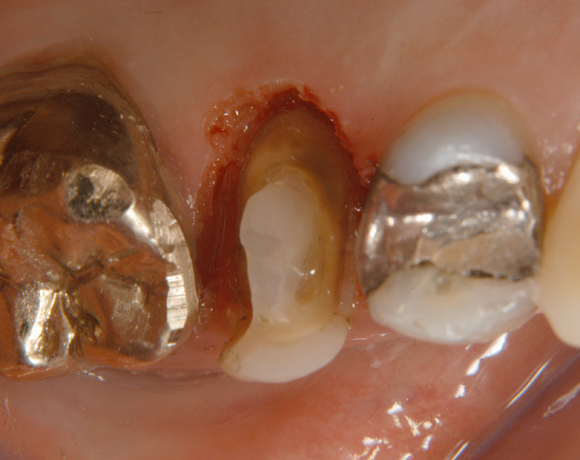

Ein Projekt aus dem Jahr 2003